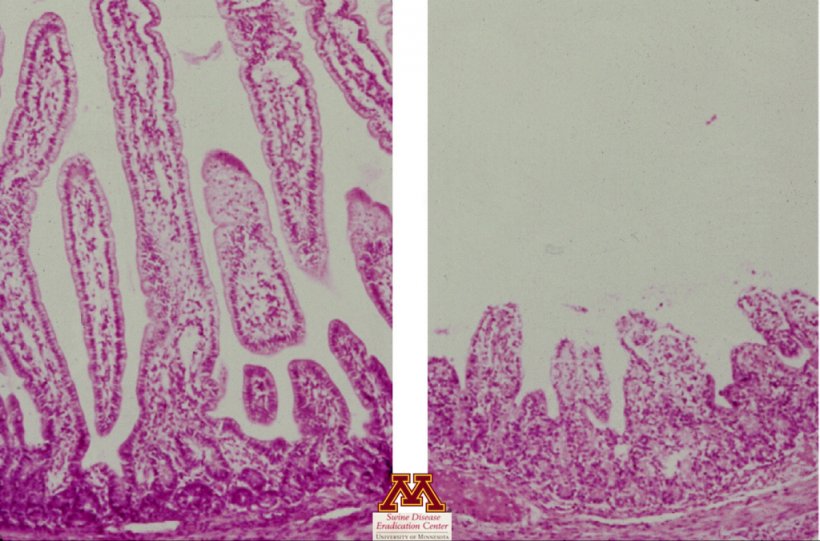

Histopathology

- Evaluates the presence of tissue lesions (small intestinal villus atrophy) which will strongly counsel the presence of illness

- Pattern varieties: jejunum and ileum tissue

- Ascertain villus atrophy suggesting viral enteritis

Histopathology

- Sure: Affirmation of illness, however now not reason for illness

- Damaging: Damaging, or lesions may have been overlooked if checking out mistaken pattern or too overdue after an infection